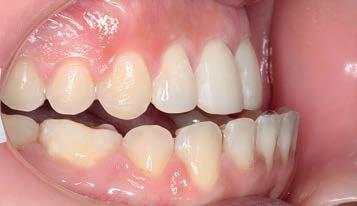

Figs. 1a–h: Initial situation: patient’s facial view (a-c); intraoral view (d-f); cephalometric X-ray (g); pantomograph X-ray (h).

A 27-year-old female patient presented for treatment exhibiting a Class II, division 1 malocclusion with a severely protrusive maxilla and a severely retrusive mandible. The patient had had previous orthodontic treatment with extraction of the lower premolars. In consultation with other orthodontists, orthognathic surgery was recommended, which she wanted to avoid.

The treatment plan was to reposition the mandible forward, placing the case into a Class I occlusion (Sagittal First) using the Carriere Motion Clear Class II Appliance, then complete treatment utilising light-force archwires in a passive, self-ligating system. The Motion Clear Appliance is the latest addition to the family of Motion appliances, designed for the patient with high aesthetic demands.

Figs. 9a–c: Situation after 1 month of correction with Sagittal First approach. – Figs. 10a–c: Situation after 2 months of correction. – Figs. 11a–c: Situation after 3 months of correction: Class I achieved. – Figs. 12a–c: Situation after 4 months of treatment (3 months of Motion sagittal treatment and 1 month in fixed appliances). .014 x .025 wire with power chain to close the spaces between the incisors. – Figs 13a–c: Situation after 7 months of treatment (3 months of Motion sagittal treatment and 4 month in fixed appliances). .019 x .025 archwire was engaged with power chain to retract the anterior segment and bring it into the final desired position. – Figs 14a–c: Final situation achieved after 11 months of treatment (3 months of Motion sagittal treatment and 8 months of Carriere SLX fixed appliance therapy).

Figs. 15a–g: Comparison of pre- and post-treatment situations. Cephalometric X-rays: initial situation (a); after 3 months of correction – Class I achieved (b); final result (c). Patient’s facial lateral view: initial situation (d); comparation of pre- and post-treatment situations (e). Post-treatment intraoral situation: buccal view lower forward movement (f); central view lower forward movement (g).